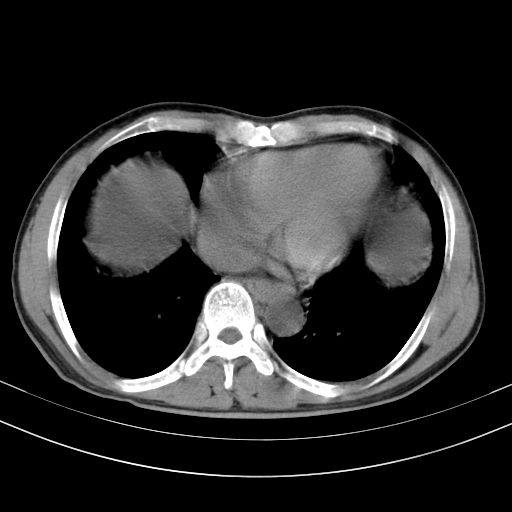

以下是引用随光逐影在2010-2-28 10:23:00的发言:[br]1)考虑肝癌;建议行ct增强扫描检查。2)肝硬化,脾大,腹水。3)慢性胆囊炎。

以下是引用dyqct在2010-2-28 16:44:00的发言:[br][quote]以下是引用随光逐影在2010-2-28 10:23:00的发言:[br]1)考虑肝癌;建议行ct增强扫描检查。2)肝硬化,脾大,腹水。3)慢性胆囊炎。